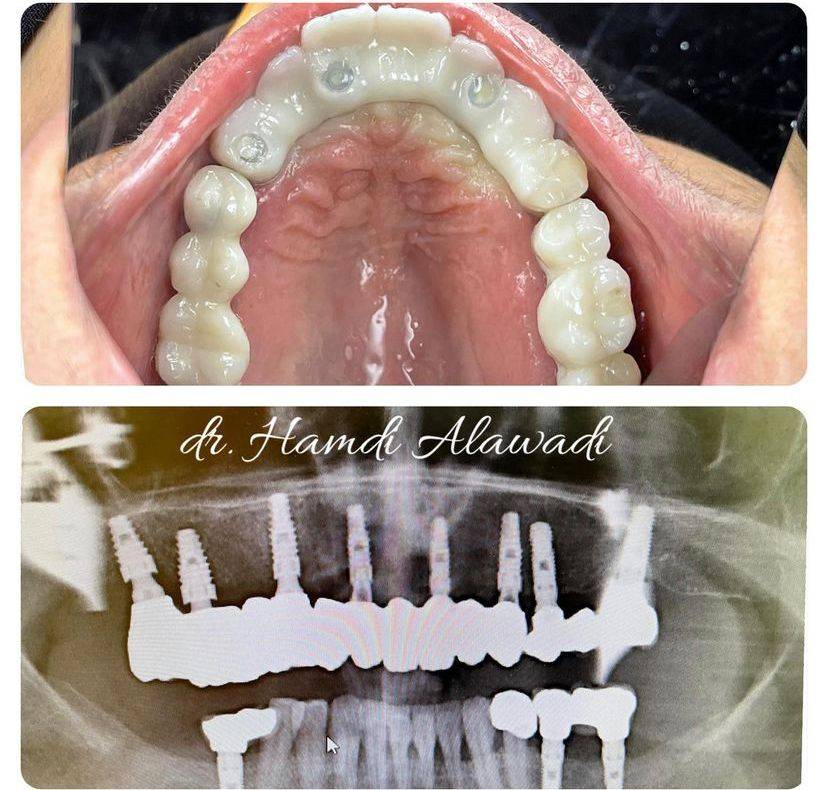

الدكتور حمدي العوضي

تخرج الدكتور حمدي العوضي من كلية طب الأسنان في عام 2003 ، وأنهى فترة تدريبه ، وعمل على الفور في مستشفى اليمامة (وزارة الصحة) حيث عمل كممارس أسنان عام لمدة 4 سنوات.

ثم بدأ درجة الماجستير في جراحة الفم والوجه والفكين وتخرج بدرجة الشرف حيث كانت رسالته الماجستير حول أنواع وإجراءات ترقيع العظام المختلفة.

أجرى الدكتور حمدي العوضي أكثر من 50.000 عملية زراعة أسنان وترقيع عظمي خلال السنوات العشر الأخيرة من ممارسته.